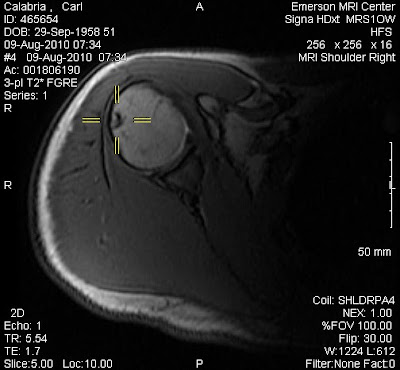

It did not take long for Kyle and Nico to find a game of beach volleyball and only slightly longer for me to join them. With my torn rotator cuff I cannot spike or serve over hand but I can still bump and set fairly well. Few things bring more joy to a father than sharing a game he loves with sons who have become his equal.

Today was spent poolside and at the beach. Jeanine participated in a water aerobics class while I took advantage of the pool to do some rehab on my shoulder. Kyle made arrangements to get his passport tomorrow and will fly down to join us on Thursday morning. We got a preview of life when he leaves for college and it must be said that we all miss him.